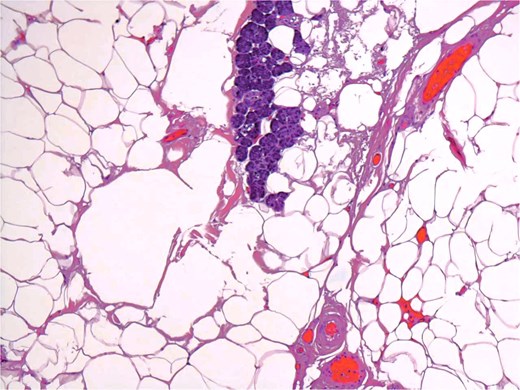

A 54-year-old male presented for assessment of a non-tender swelling in the left parotid region. His past medical history was unremarkable. Neck magnetic resonance imaging (MRI) revealed a well-defined adipose lesion in the left parotid gland measuring nearly 4.6 cm in its largest dimension. Neck ultrasound (US) additionally revealed bilateral thyroid nodules; Fine-needle aspiration of the right thyroid nodule confirmed benign follicular changes (Bethesda class II). Follow-up imaging (MRI and US) 1 year later showed a stable parotid lesion measuring 5.3 × 3.2 × 2.8 cm without contrast uptake. Bilateral thyroid nodules were unchanged. The patient was asymptomatic but reported cosmetic worries. Repeat imaging MRI demonstrated mild progression to 4.8 cm, expanding toward the parapharyngeal space. The lesion displayed uniform fat signal with no malignant enhancement. In view of gradual enlargement and patient cosmetic concern, surgical excision was recommended. A complete left parotidectomy with full general anesthesia was performed. During surgery, a lobulated, soft tumor measuring 6 × 4.5 × 2 cm was excised, while sparing all facial nerve branches. No complications were noted. Microscopic examination revealed a lobulated fibro-fatty tumor consisting of well-differentiated adipose tissue with intermixed salivary gland acini and ducts (Figs 1 and 2), establishing the diagnosis of sialolipoma. Postoperative recovery occurred without complications, and the patient showed normal facial nerve function at follow-up.

Small groups of acini, randomly distributed in lipomatous tumor.

Groups of acini and occasional ducts present within the lipomatous tumor.